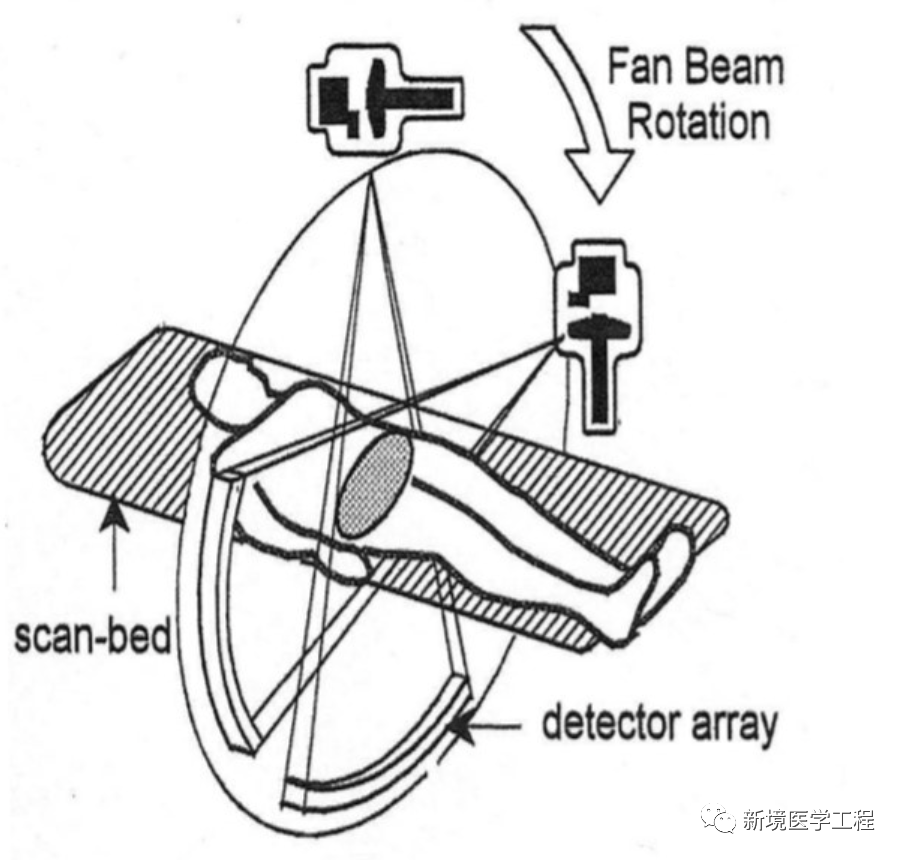

与常规X射线成像设备相比,CT系统本质上更容易产生伪影:一个CT图像是由大量投影生成的。在一个典型的CT系统中,每个投影包含大约1000个单独的测量,在多层CT的情形下,形成一幅图像需要使用10E19个独立信号读取或测量!由于反投影过程的本质是将投影中的一点映射到图像中一条直线(如下图),投影读数的一个误差不像常规射线照相的情况,不再局限于局部区域。因为测量的不准确通常表现为重建图像中的误差,所以CT产生伪影的概率明显偏高。